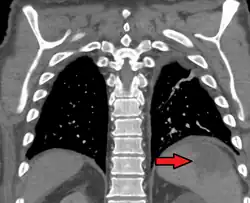

Splenic infarct seen on CT | |

Splenic infarction is a condition in which blood flow supply to the spleen is compromised,[1] leading to partial or complete infarction (tissue death due to oxygen shortage) in the organ.[2] Splenic infarction occurs when the splenic artery or one of its branches are occluded, for example by a blood clot.[3]

An abdominal CT scan is the most commonly used modality to confirm the diagnosis,[3] although abdominal ultrasound can also contribute.[5][6][7]